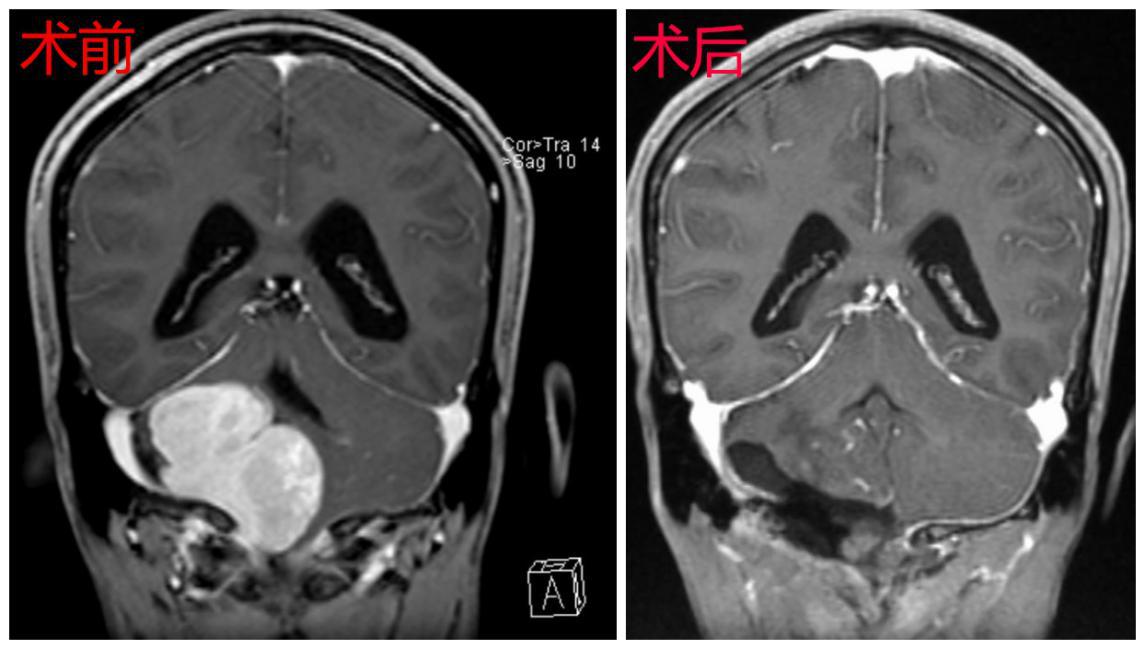

术前术后对比图

在尚未联系深圳市第二人民医院之前,曾先生病情急转直下,突然出现急性脑积水、高颅压、脑疝昏迷等症状,2018-04-01在当地医院急诊行“脑室外引流术”,然而这仅是权宜之计。曾先生家属根据北京天坛医院专家意见联系深圳市第二人民医院脑科中心医师后于2018-04-03转入我院,由神经肿瘤病区颅底组接收了曾先生。深圳市第二人民医院脑科中心主任、颅底肿瘤协作组组长蒋太鹏教授组织颅底组成员王建中副主任医师、林恒州副主任医师、左大辉主治医师、刘晓佳主治医师对曾先生病情进行全面评估发现,曾先生的复发肿瘤病理为“恶性孤立性纤维性肿瘤”,肿瘤目前已侵占右侧枕骨大孔区、桥小脑角区、斜坡、天幕及鞍上等部位,病变范围广泛,该肿瘤供血极其丰富。

因肿瘤生长区域有众多重要血管及颅神经通过,还压迫生命中枢脑干,解剖结构复杂,且既往有手术病史,肿瘤粘连严重,可能包绕各颅神经和重要血管,手术难度极大,术中极易损伤重要颅神经及血管,而且一次性完全切除肿瘤极其困难,术后也极易出现呼吸障碍、面瘫、吞咽障碍、昏迷、四肢瘫痪等严重并发症。对于医生来说这是一个非常棘手的病例,施行手术是一个极大的挑战。考虑到患者已辗转国内外多家医院均未得到有效救治,放弃手术即等于放弃生命,通过详细告知家属病情,家属表示积极配合治疗,在此基础上神经外科全体医师进行再次讨论,得到了神经外科首席专家高永中教授和全体医师的支持,并制定了详细的手术治疗方案及应急预案。

考虑到曾先生的脑室外引流管已留置3天,未来的3天为清明小长假,若等节后手术会增加颅内感染风险。随即蒋太鹏教授将患者病情通报手术室钮敏红、龚喜雪两位护士长及麻醉科杨新平副主任,她们表示全力配合为患者进行手术。时间就是生命,2018.04.05清明节放假第一天全体医护人员放弃休息,为曾先生施行手术。术中肿瘤供血极其丰富,在分离三叉神经和迷走神经周围肿瘤时曾出现“脑心反射”致患者心跳骤停,幸好丰富经验的手术团队及时处理,手术得以继续进行,历时约12小时,是一场不折不扣的拉锯战,对医师的精力、体力有极大的要求,手术顺利将肿瘤近全切除,将患者生命从死神的手中重新夺回。